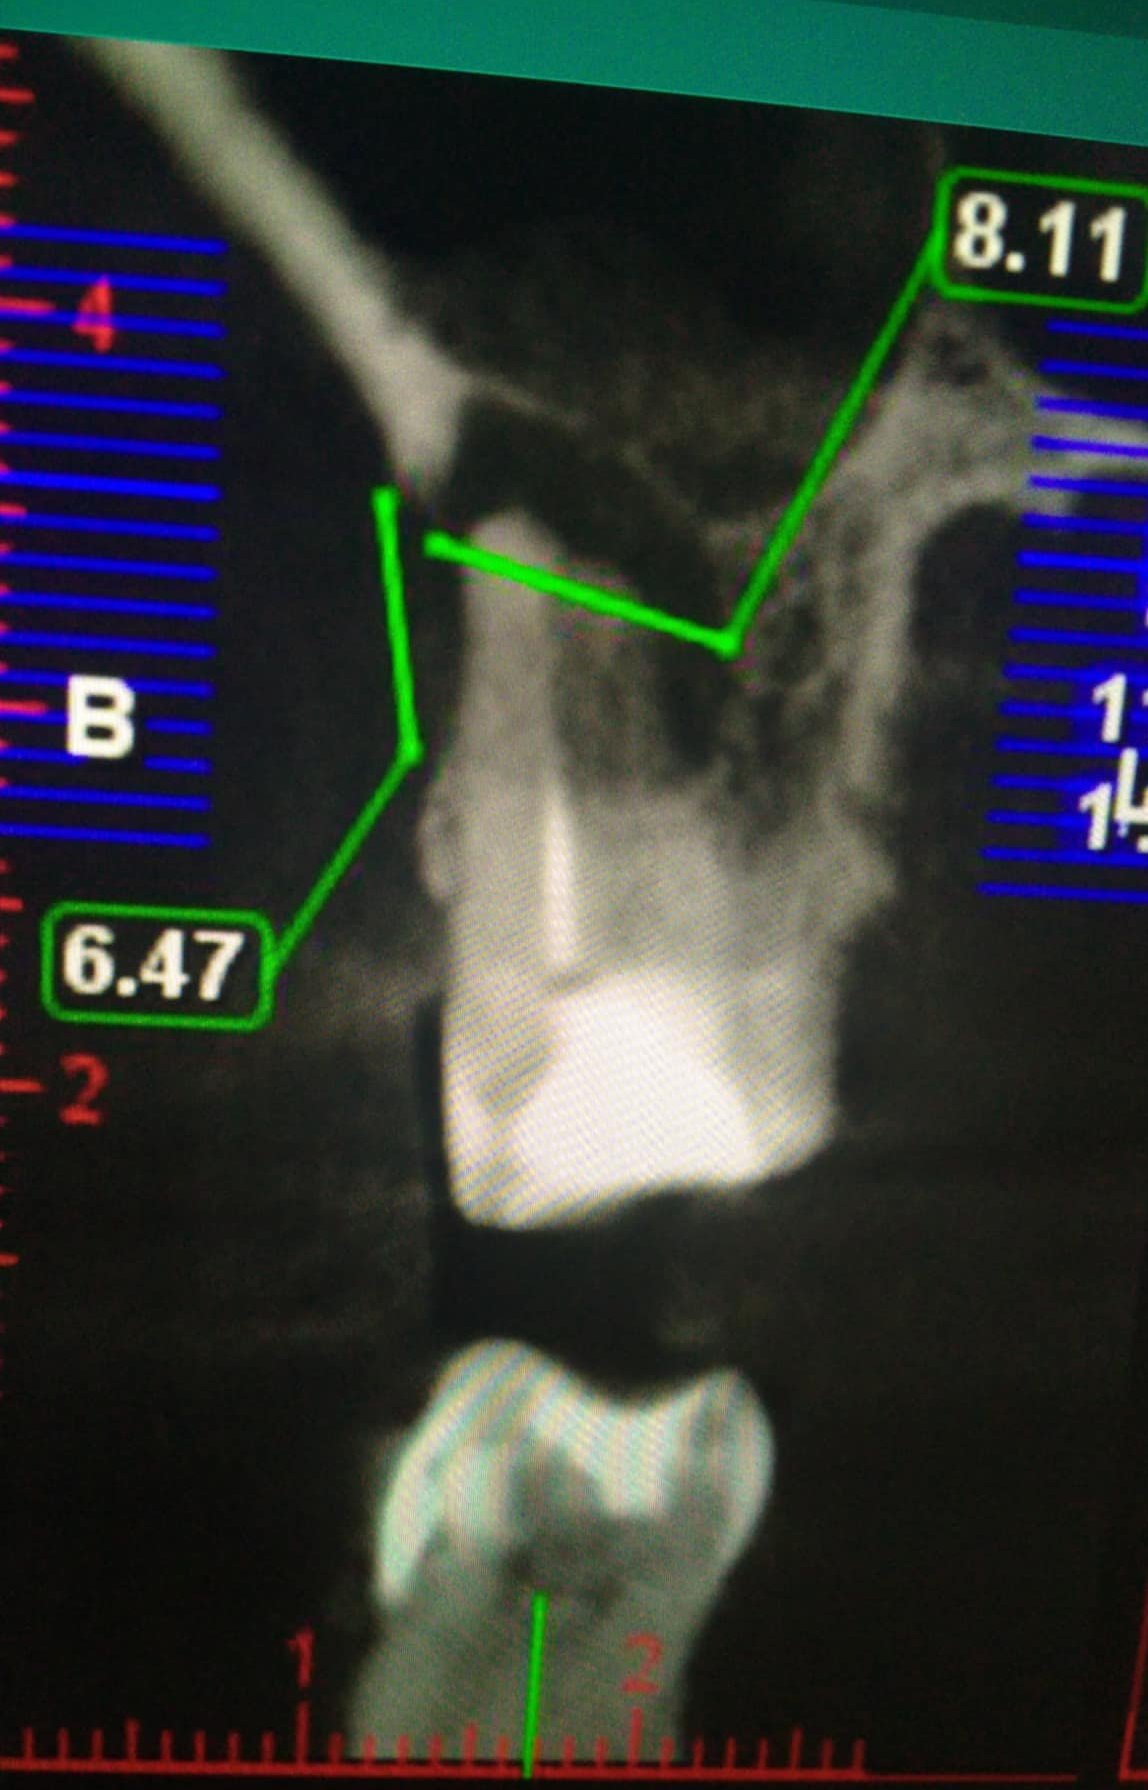

Ето това се видя на 3Д КТ.